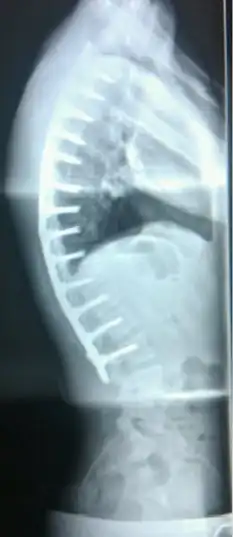

![]() Paciente de 20 años con la enfermedad de Scheuermann, con diversas medidas de la cifosis y la lordosis | ||